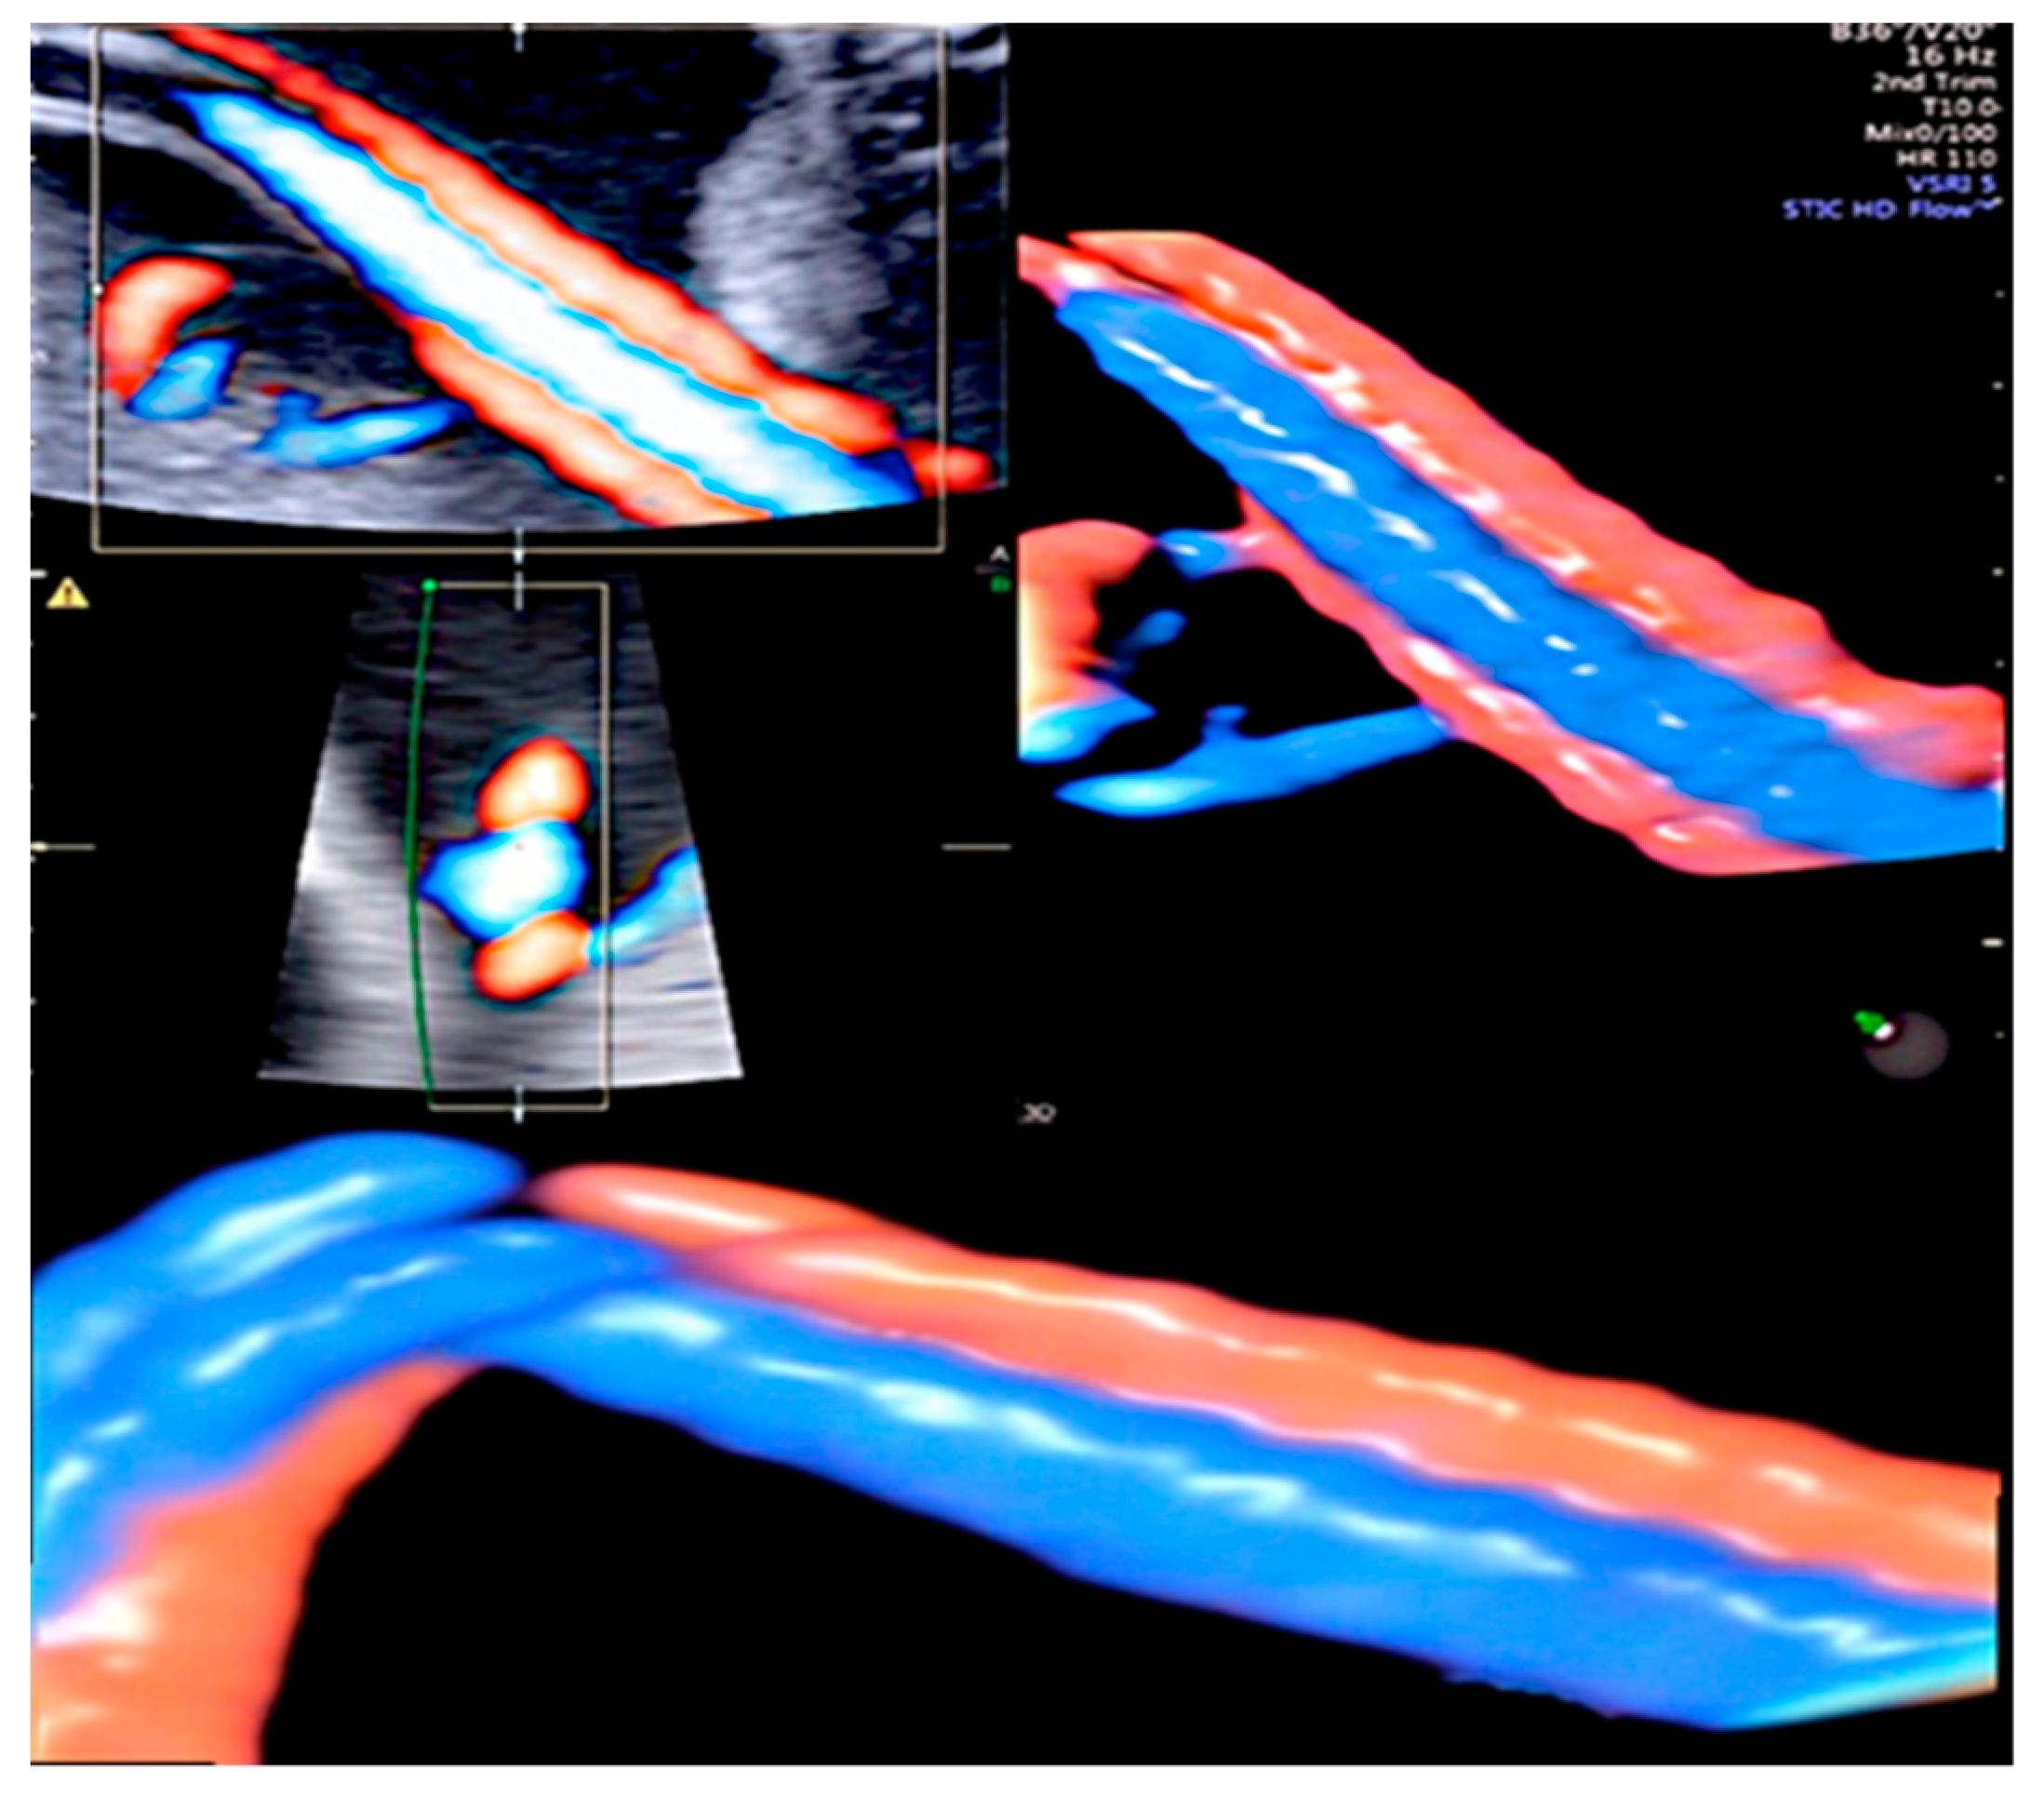

3.1. Cord Coiling